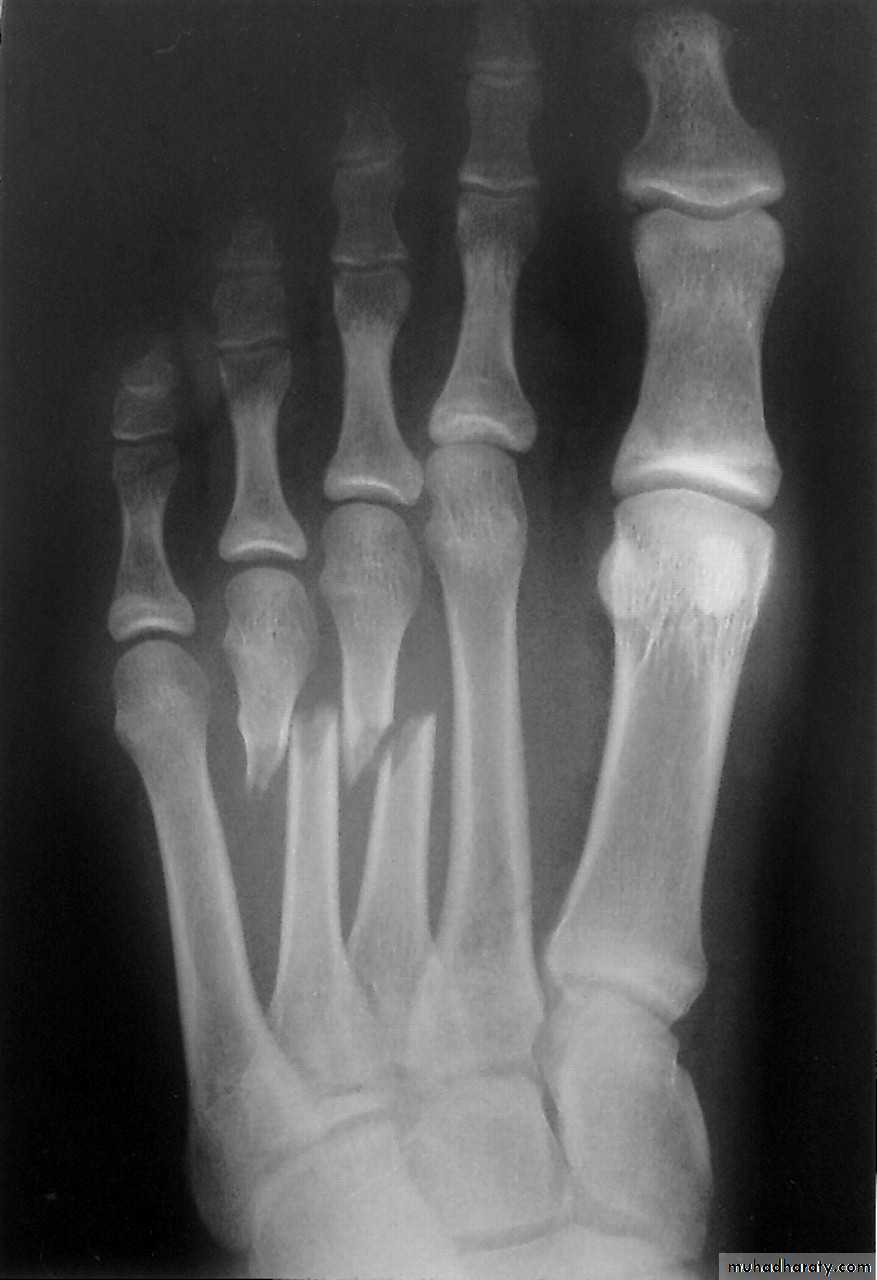

Фото 3г. Рентгенограмма. Перелом костей плюсны у собаки. Внеочаговый остеосинтез аппаратом Илизарова (до и после операции).